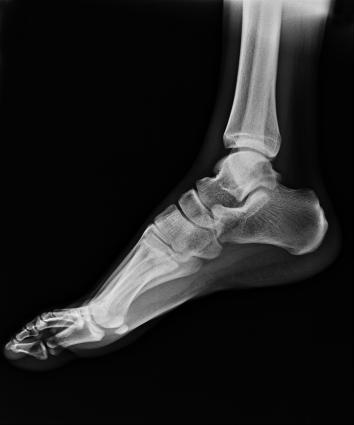

● 可快速選擇、預(yù)設(shè)所需要的視野,節(jié)約擺位時(shí)間;

● 根據(jù)拍攝需求或技師使用習(xí)慣一鍵切換光束范圍;

● 可根據(jù)不同的體位協(xié)議,自動(dòng)調(diào)整光束大小。